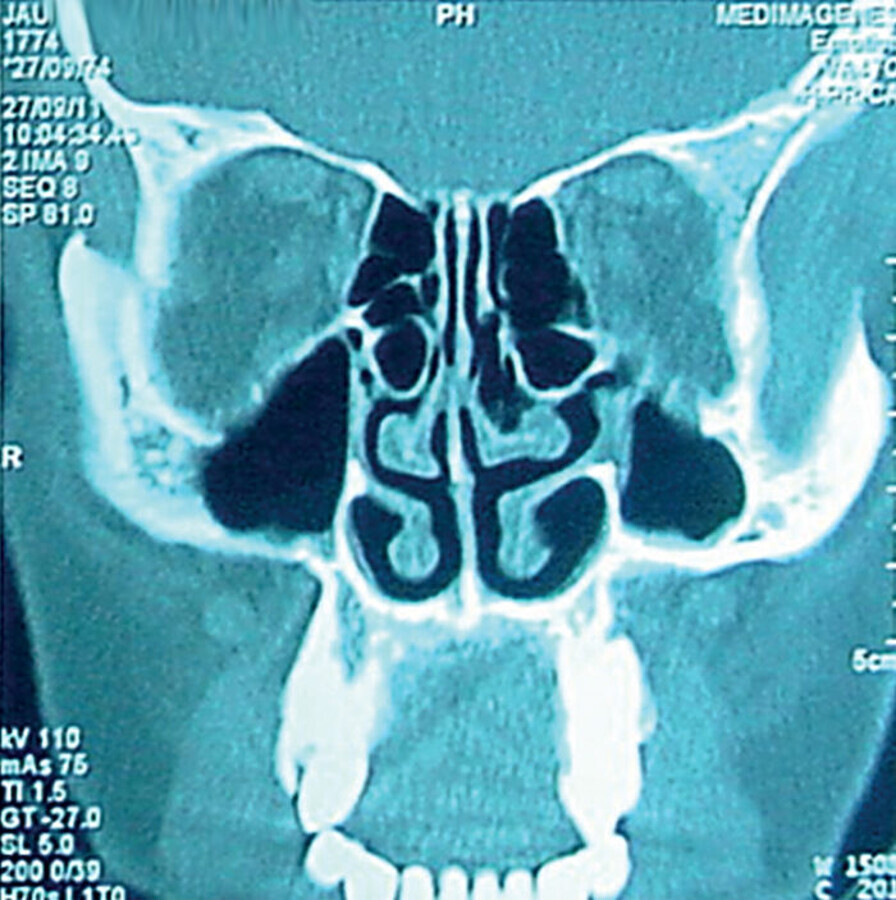

Figura 2. Poliposis nasosinusal vista por TC. (Colaboración: Dr. ORL. Vinicio Toscano)

Poliposis deformante o síndrome de Woakes: es un síndrome que presenta una etmoiditis deformante del macizo facial por ensanchamiento de la pirámide nasal provocado por poliposis nasal desde la infancia.